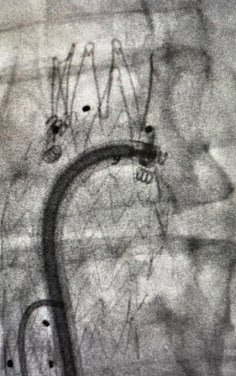

Antes: Oclusión bilateral ilíaca

Antes

Oclusión de ambas venas ilíacas/Sindrome de congestión pélvica

Después: Reconstrucción con stents

Después

Reconstrucción con stents. Flujo normalizado y resolución clínica.